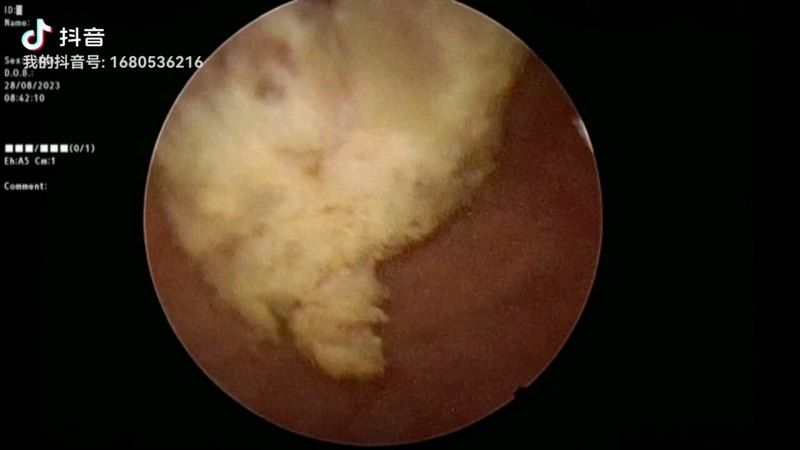

- 患者:女 50岁最后交流时间 02.07现在医生在吗总交流次数7已给处置建议

- 乳腺增生 第一张是我单位体检的报告,后一张是今天做钼靶的报告,姚医生帮... 后期需要我做什么,严不严重,需不需要干预总交流次数9已给处置建议

- 甲状腺结节 甲状腺术后五年每天吃1.5粒药,是否需要改变药量 这是7... 我是术后五年,现在药量是每天1.5粒,请问这个药量需要变吗?总交流次数7已给处置建议

- 甲状腺乳头状癌术后 甲状腺癌术后复查,请姚医生帮看一下用药是否需调整,现每天用量... 复查结果是否正常?总交流次数3已给处置建议

- 21年甲状腺癌半切 第一张是22年11月早上空腹未吃优甲乐测的,第二张是今天早晨... 需要调药,还是如何处理总交流次数12已给处置建议